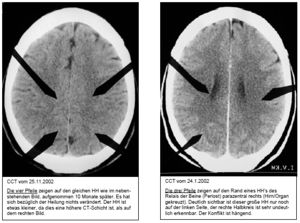

Der unbekannten NM-Ärztin erzählte Buck von einem "hochakuten, dramatischen und isolierenden" Verlustkonflikt aus dem Sommer 2001, den er durch wochenlange Gebete angegangen habe, der im Oktober 2001 wie durch ein Wunder aber "gelöst" worden sei. Laut Buck habe die Ärztin daraufhin "bestätigt", dass der genannte "Verlustkonflikt" eindeutig die Ursache des vermeintlichen Hodentumors sei. Zur NM-Diagnostik musste Buck zum Radiologen um ein Schädel-CT anfertigen zu lassen, um nach Hamerschen Herden zu fahnden. Im weiteren Verlauf stellte sich heraus, dass ein positiver Tumormarkerwert im Blut nicht zu finden war. Die NM-Ärztin soll dann an Hand des CT "festgestellt" haben, dass der gemeinte Konflikt in Lösung sei und dass es sich um ein "interstitielles Hoden-Carcinom" handeln müsse, das dabei einer Nekrose entspreche, die während der konfliktaktiven Phase Zellminus bewirkt. Laut NM-Ärztin befände Buck sich in einer "Heilungs-Phase (pcl-Phase)" und im CT seien keine "aktiven Hamerschen Ringe" zu sehen. Im April 2002 ging dann Buck dennoch nach Absprache mit der NM-Ärztin zu einem Urologen, da sich Schmerzen einstellten. Der Urologe soll ihm erzählt haben, dass er mit einer "Wahrscheinlichkeit von 95%" einen Hodentumor hätte (berichtete Diagnose: Die Untersuchung zeigte einen auffällig indurierten[18] Nebenhoden/Hoden rechts, Nebenhoden vom Hoden nicht sicher abgrenzbar, dringend tumorverdächtig.), der chrirurgisch gehandelt eine nahezu 100%ige Heilung erwarten liesse. Buck machte sich nun Sorgen aufgrund der für ihn schockierenden Diagnose Metatstasen zu bekommen, da laut Hamer so genannte Zweitkrebs nach "Diagnoseschock" auftreten würden. Eine Frau Kerti Nebelsiek (offenbar keine Ärztin sondern Biologiestudentin und Hameranhängerin) schrieb ihm in einer Email: auf jeden Fall weder eine Chemotherapie noch eine Bestrahlung machen zu lassen. Als die Laborergebnisse eintrafen, und die Tumormarker AFP, β-HCG, als auch PLAP negativ waren, revidierte der Urologe seine vermutete Diagnose. Ein Seminom oder ein bösartiger Tumor seien unwahrscheinlich und empfahl eine Biopsie (Probeentnahme). Inzwischen hatte ein NM-Heilpraktiker der sich "in der neuen Medizin auskenne", ebenfalls seine Schädel-CT Aufnahmen angesehen. Dieser Heilpraktiker rief ihn an und meinte dass er aufgrund der CT-Bilder "wisse", dass es sich um ein "interstitielles Hoden-Ca aufgrund eines Verlustkonfliktes" handele. Er könne auch feststellen, dass der Konflikt "in Lösung sei". Ausserdem könne er einen "brutalen Trennungskonflikt" im CT befunden und schlug eine weitere CT-Aufnahme vor. Auch dieses CT soll dann gezeigt haben, dass sich der angenommene "Hodentumor" in eine "Heilungsphase" befinde", da ein Hamerscher Herd im CT "in Lösung" sei. Es sei nur noch eine "Ödematisierung" erkennbar. Daraufhin besserte sich der Zustand und Buck beschloss Mitglied im Verein "Menschen gegen Krebs e.V" zu werden, um regelmäßige Infos zum Thema Krebs und alternativen Krebstherapien zu erhalten. Außerdem könne er so als Mitglied täglich bei der Info-Hotline anrufen und Fragen an Herrn Hirneise stellen. Hirneise soll ihm dann von einer erwogenen Misteltherapie abgeraten haben, da diese "den Körper nur unnötig belaste". Eindeutige Beweise zur Wirksamkeit dieser Therapie gäbe es derzeit sowieso noch nicht laut Hirneise. Buck: Er bestärkte mich in meinem Glauben an die Richtigkeit der Neuen Medizin. Er sagte, dass ich das Glück gehabt hätte, von der ersten Minute an nach der Neuen Medizin vorgegangen zu sein. Die meisten Menschen würden erst nach Alternativen suchen, wenn sie von der Schulmedizin aufgegeben sind.